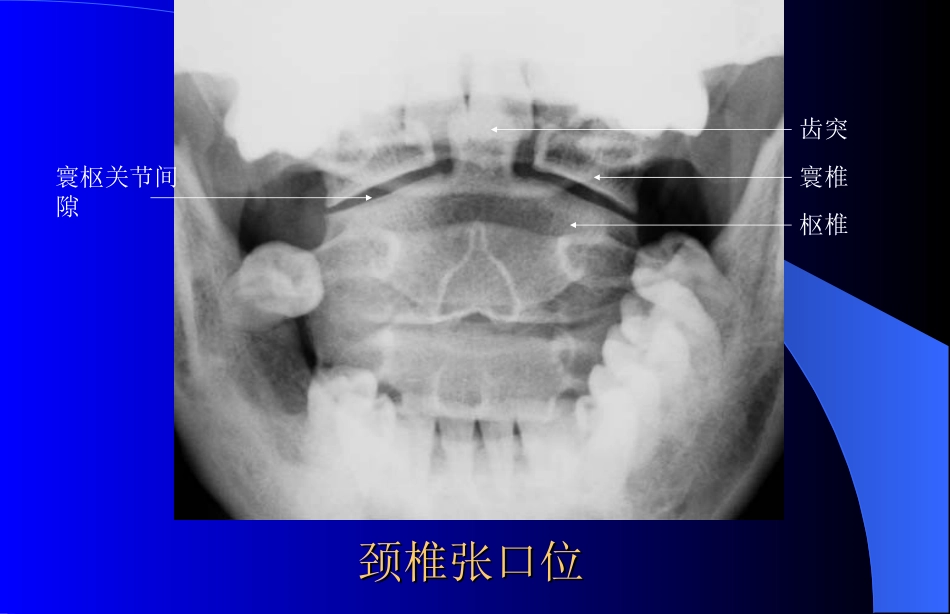

颈椎张口位颈椎张口位摄影目的:观察寰、枢椎的正位情况摄影体位:仰卧,头正中矢状面与床面中线一致并垂直于床面。头稍后仰,牙齿咬合面与乳突尖连线垂直台面。曝光时尽量张口,保持头部稳定。中心线:经两口角连线中点垂直射入。照片显示:从口腔中清晰显示一、二颈椎的前后位影像标准片显示标准片显示寰、枢椎显示于上、下齿之间上中切牙牙冠与枕骨底部相重,第2颈椎齿突不与枕骨重叠牙突与第一颈椎两侧间隙对称,寰枕关节呈切线状显示寰、枢椎骨纹理显示清晰颈椎张口位颈椎张口位寰椎枢椎寰枢关节间隙齿突颈椎前后位颈椎前后位摄影目的:观察第3~7颈椎的正位影像摄影体位:仰卧于摄影床上或站立于摄影架前,头正中矢状面与床面(胶片)中线一致,并垂直于床面。头稍后仰,颌部抬起。中心线:向头侧倾斜10°~15°角,对准甲状软骨下方射入探测器中心。照片显示:第3~7颈椎的正位影像标准片显示标准片显示第3~7颈椎与第1胸椎投影于照片中颈椎棘突位于椎体正中,横突左右对称椎间隙与钩突关节显示清晰气管投影于椎体正中下颌骨位于第2、3椎间隙水屏高度显示第3~7颈椎骨纹理显示清晰第2颈椎第3颈椎第4颈椎第5颈椎第6颈椎第7颈椎椎体横突棘突椎间隙椎弓根枕骨第1胸椎第1肋骨颈椎正位颈椎正位颈椎正位颈椎正位气管颈椎侧位颈椎侧位摄影目的:观察全部颈椎的侧位影像摄影体位:仰卧于摄影床上或站立于摄影架前,头稍后仰,下颌抬起,听鼻线与探测器上缘平行。两肩下垂,颈部正中矢状面与探测器面平行。中心线:经下颌角向下2cm处水平射入。照片显示:颈椎椎体、棘突、椎间隙及软组织、舌骨清晰显示标准片显示标准片显示第1~7颈椎序列以正常生理曲度显示照片正中下颌骨不与椎体重叠各椎间隙及椎间关节显示清晰、边缘锐利气管、颈部软组织与椎体层次可辩椎体骨纹理清晰显示颈椎侧位颈椎侧位寰椎枢椎上关节突下关节突第7颈椎棘突齿突下颌骨颈椎侧位颈椎侧位颈椎前后斜位(左右)颈椎前后斜位(左右)摄影目的:观察椎间孔、小关节及椎弓根的情况摄影体位:患者直立于摄影架前,背向暗盒,身体的正中面与暗盒成45°角,颏部内收,头向被检侧外旋,使头部的矢状面与暗盒平行中心线:第4颈椎照片显示:颈椎斜位影像,椎间孔及椎弓根清晰显示标准片显示:第1~7颈椎显示于照片正中椎间孔呈卵圆形,边缘锐利下颌骨与椎体不重叠椎体骨纹理清晰显示颈椎椎间孔前后斜位颈椎椎间孔前后斜位椎间孔椎弓根第7颈椎枢椎棘突